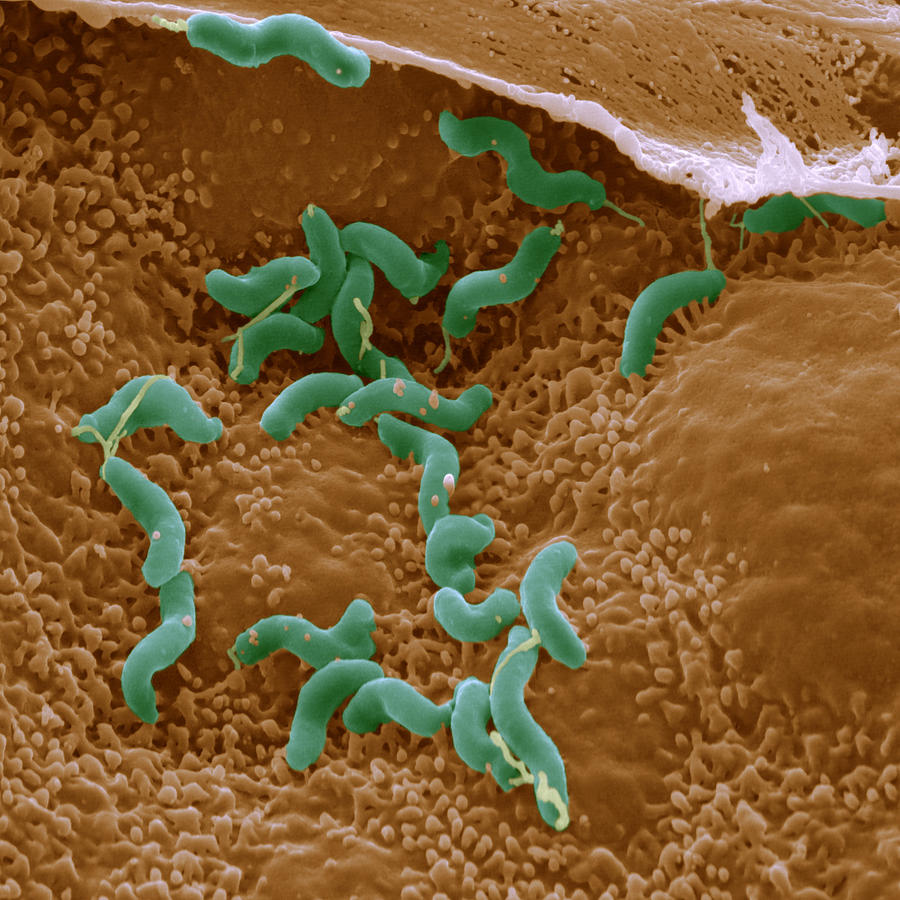

Кампилобактер фетус: патогенез и инфекции

Раздел: Другие животные